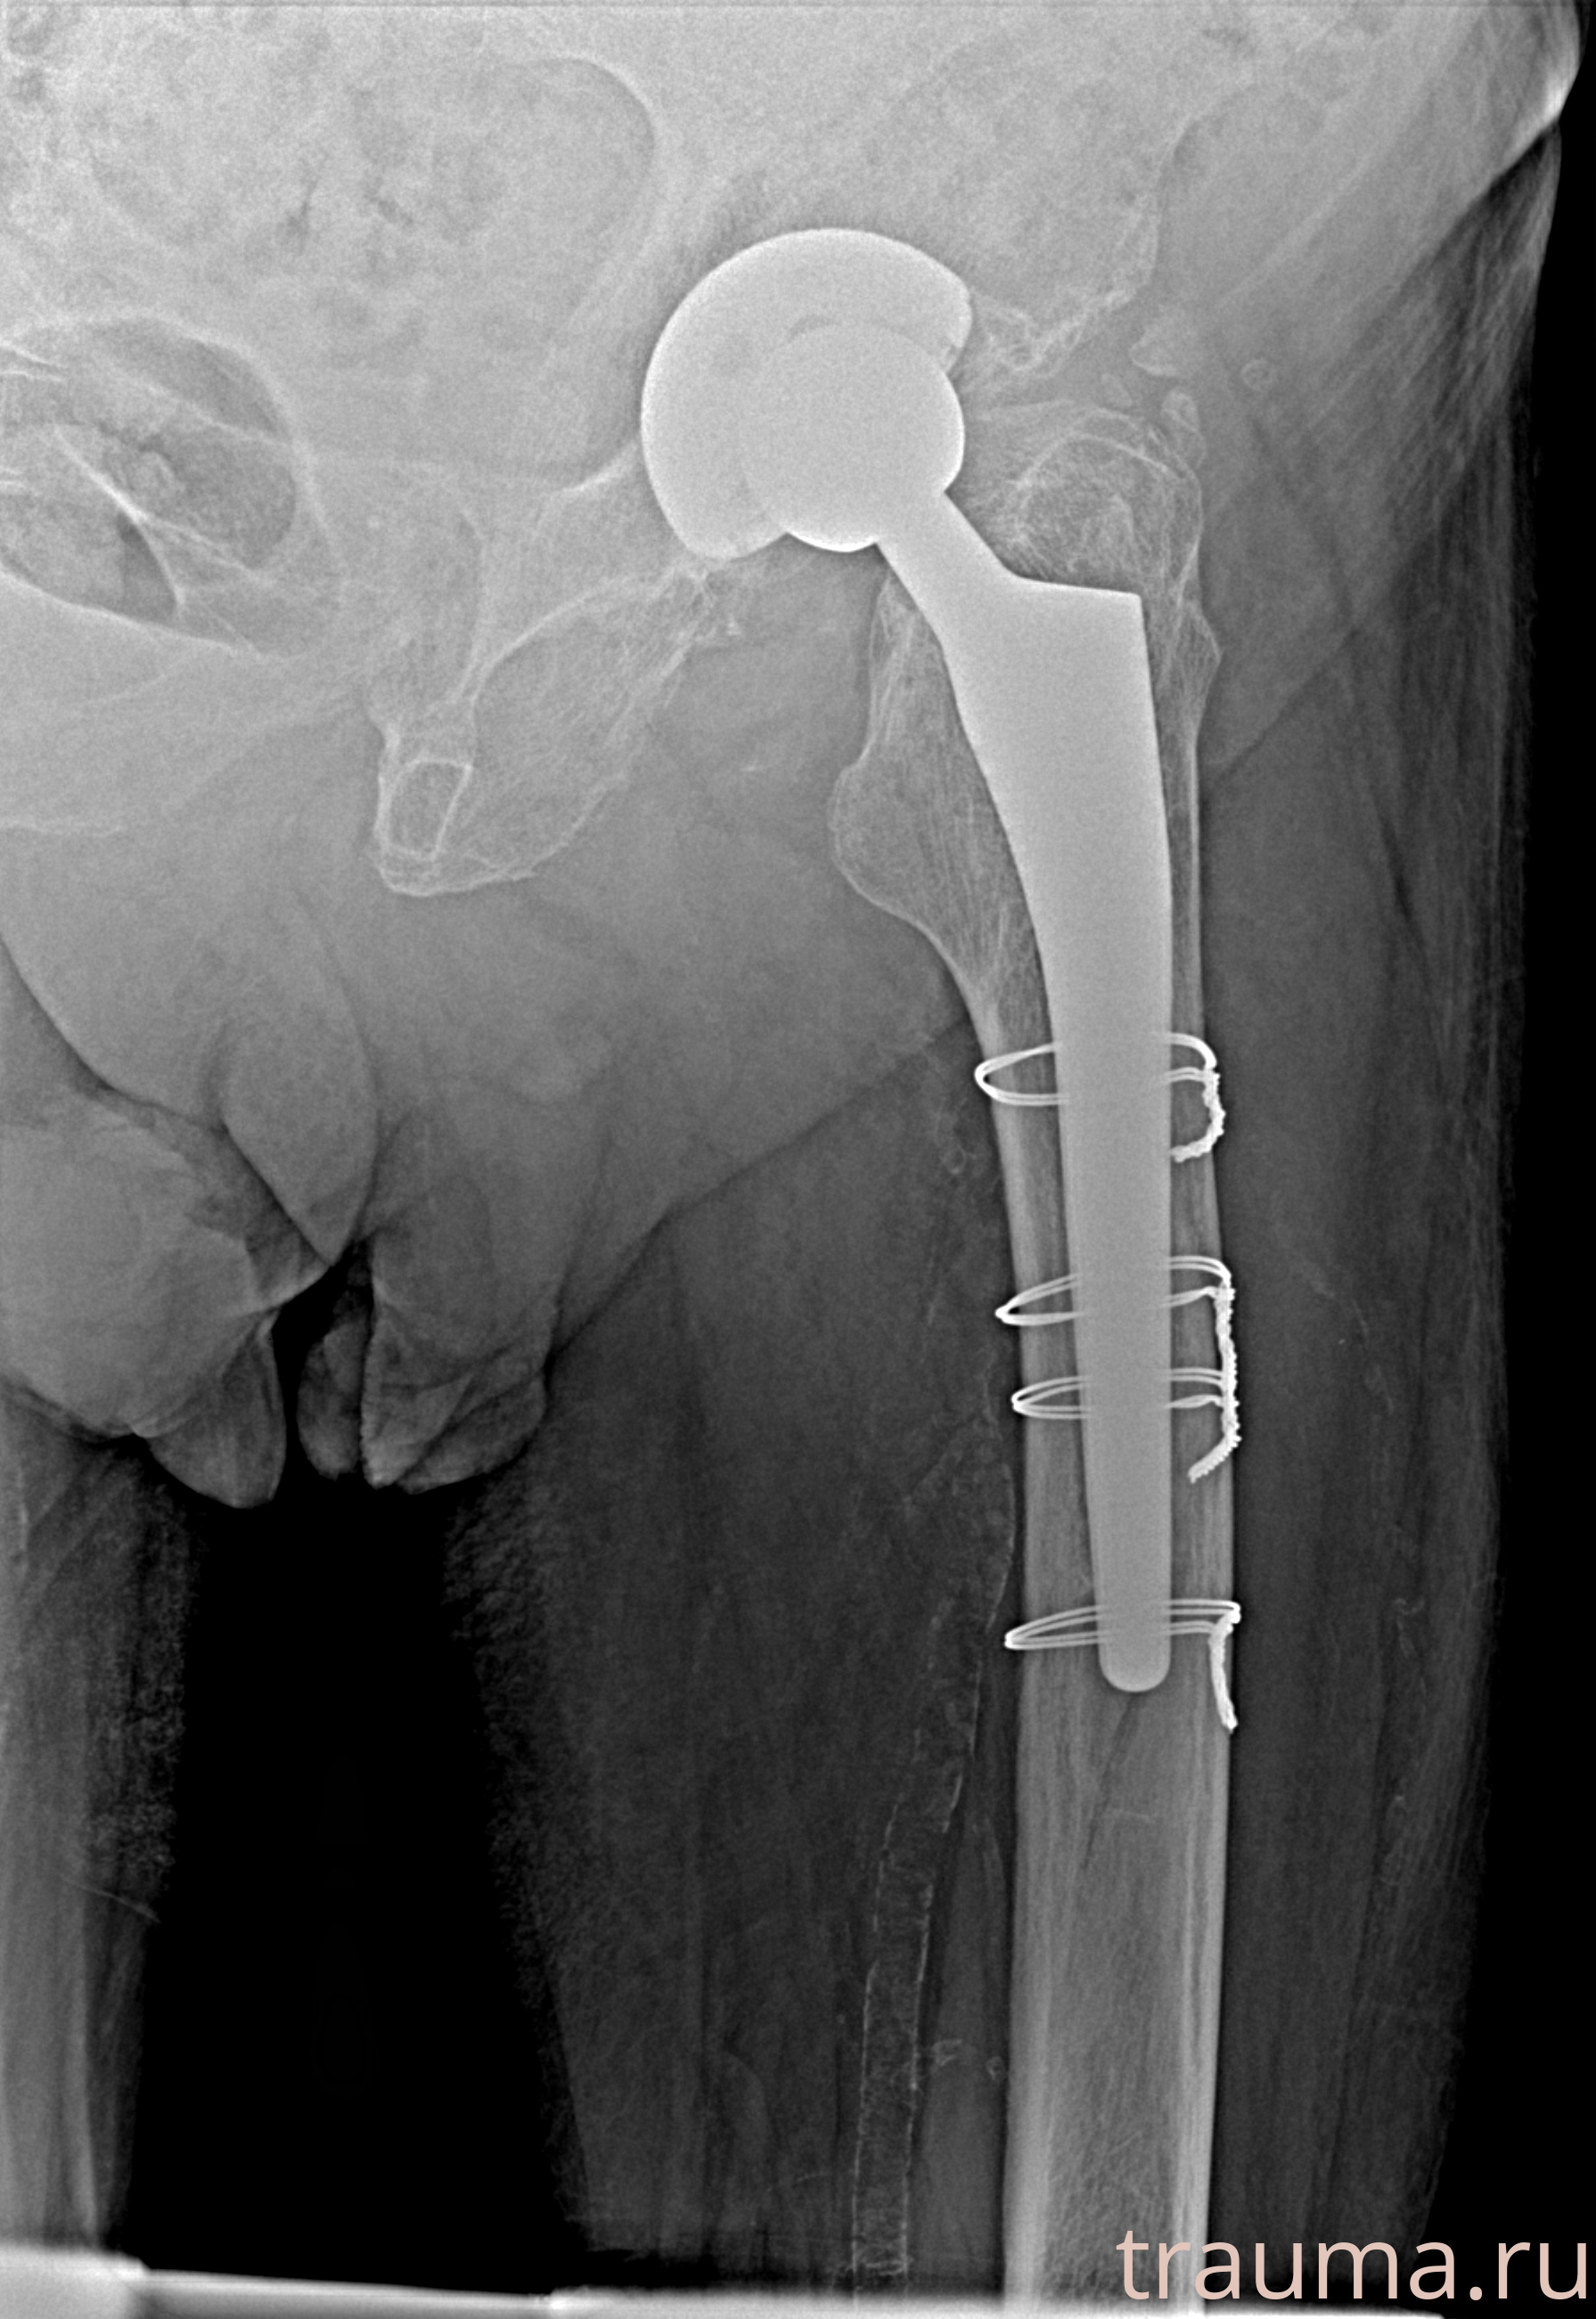

Рентгенограммы